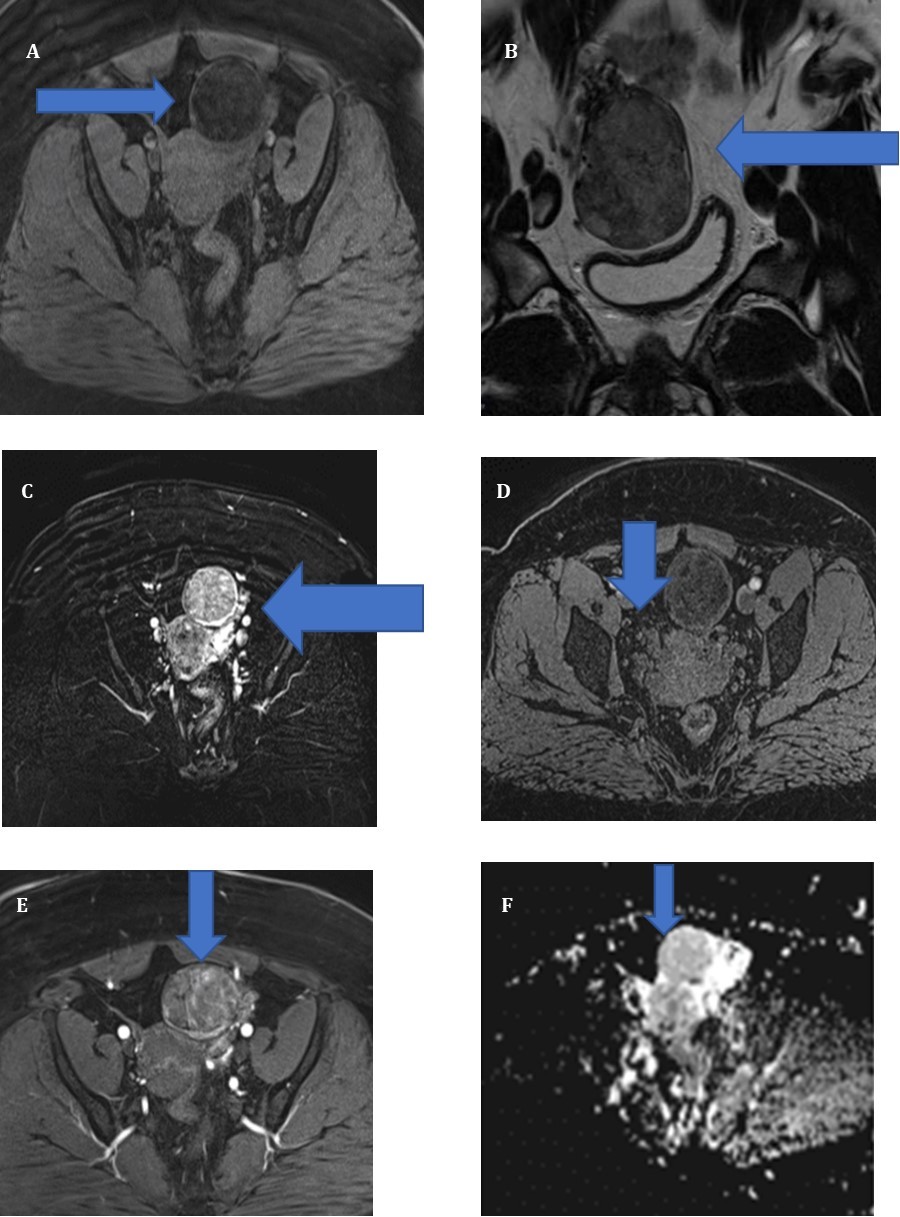

Une IRM realized without and with contrast Gadolinium, in sequence T1,T2, DIFFUSION and confirmed one left masse ovarian

(Figure 1) , ( A, B) Axial T1-Weighted image shows (6 cm) ovoid hypointense masse (arrows) in left adnexal region. Ill- defined area of high signal intensity is noted, indicating lipid content. On T2-weighted image, masse (arrows) is heterogeneously hyperintense(C). After gadolinium administration, T1-weighted image shows tumor (arrows) is very intensely enhanced (D,E,F). F, diffusion image

Figure 1A.Sequence T1 without contrast B) Sequence T2 without contrast c) T2 with contrast GADO D) Sequence T1 with contrast GADO E) Sequence T1 with contrast GADO F) Sequence diffusion

Sequence T1 without contrast B) Sequence T2 without contrast  c) T2 with contrast GADO D) Sequence T1 with contrast GADO E) Sequence T1 with contrast GADO F) Sequence diffusion